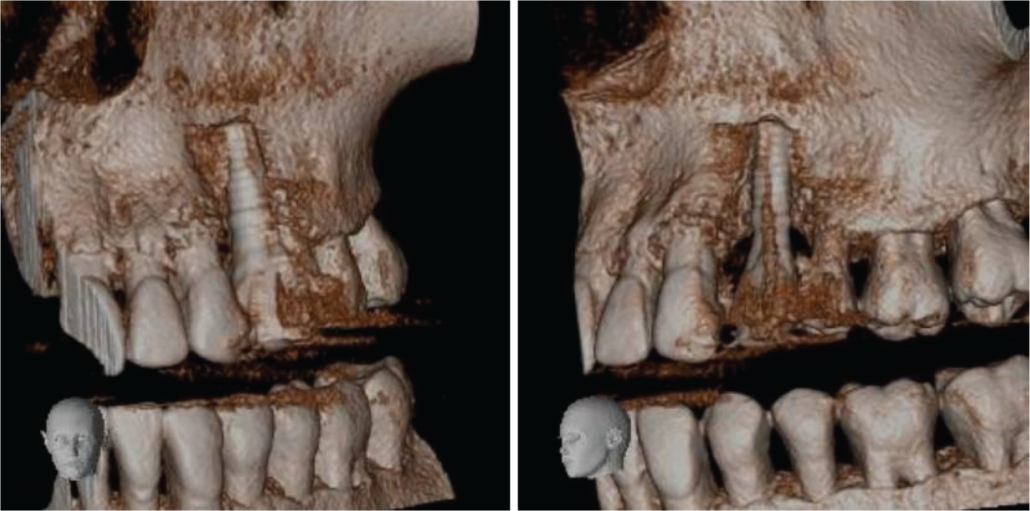

The implant shows definitive signs of failure. There are mesial, palatal and distal vertical bone defects over the coronal half of the implant and a thin radiolucent space around the apical half of the implant on those surfaces. The buccal side of the implant appears denuded of bone, although it is possible that there is some thin bone that the scan is not revealing. There is no point at which osseointegration can be inferred (images 2, 3 and 4).

Image 4. Volume-rendered images of UL4 region